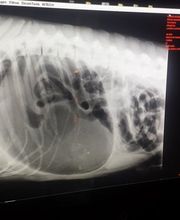

Medicina General. Cirugía. Análisis clínicos. Diagnóstico por imagen (ecografía, radiología, ecocardiografía). Traumatología. Endoscopia. ESPECIALISTAS en distintas disciplinas: Dermatología, Homeopatía y Medicina Felina.